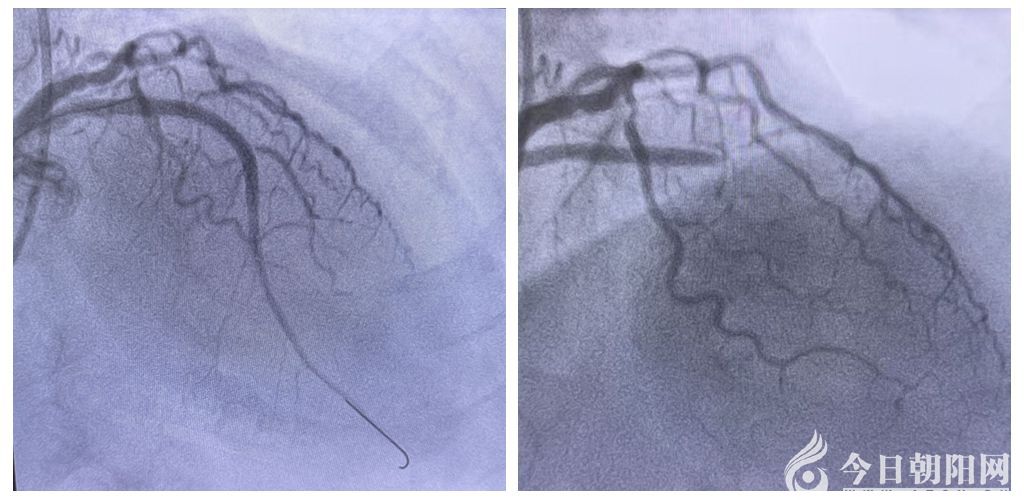

確診并接到轉(zhuǎn)診通知后,醫(yī)院胸痛中心團(tuán)隊(duì)即刻啟動(dòng)應(yīng)急機(jī)制,第一時(shí)間開(kāi)通120綠色通道,讓救護(hù)車直接將患者送往導(dǎo)管室準(zhǔn)備手術(shù)。與此同時(shí),醫(yī)院心內(nèi)科胸痛中心介入團(tuán)隊(duì)嚴(yán)陣以待,對(duì)患者實(shí)施冠脈介入手術(shù)。治療團(tuán)隊(duì)爭(zhēng)分奪秒,為患者完成血管造影、球囊擴(kuò)張及支架植入手術(shù),成功開(kāi)通了閉塞血管?;颊甙Y狀立即得到緩解,從基層衛(wèi)生院檢查到醫(yī)院心內(nèi)科救治,全程實(shí)現(xiàn)無(wú)縫銜接。術(shù)后,患者生命體征平穩(wěn),安全返回病房,目前繼續(xù)在心內(nèi)科病房接受后續(xù)治療?;鶎俞t(yī)生與上級(jí)醫(yī)院醫(yī)護(hù)人員攜手合作,成功完成這場(chǎng)與死神較量的“接力賽”,贏得了患者和家屬的肯定與感謝。